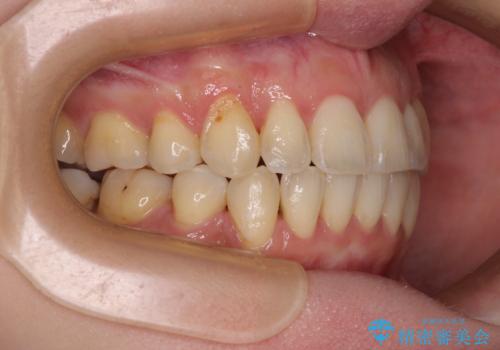

- 上下前歯のデコボコを気にして来院された患者様です。

デコボコが強いため、非抜歯で矯正をすると出っ歯仕上がりとなるため、上下左右の第一小臼歯4本を抜歯することとしました。

治療期間全体を通して歯の移動スピードがゆっくりであったので、当初予定よりも1年ほど長い、3年間を要することとなりました。